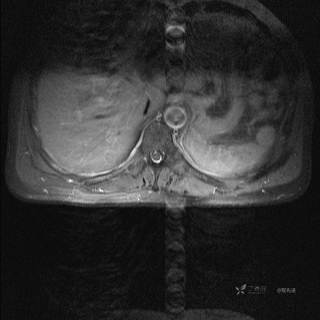

MR

T1增强冠状位

T1增强横断位